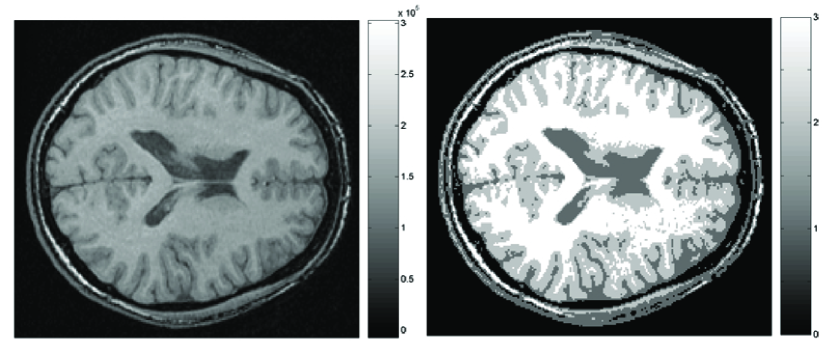

The brain MRI is a 3D array containing tissue intensity values at voxel position Figure 1 shows a usual example of axial cross-section of MRI. We usually do not analyze tissue intensity values directly in quantifying MRI. MRIs go through various image processing steps such as intensity normalization and tissue segmentation before any quantification is attempted. Image intensity normalization is required to minimize the intensity variations within the same tissue that are caused by magnetic field distortion.

Each voxel can be classified into three different tissue types: cerebrospinal fluid (CSF), grey matter and white matter mainly based on image intensity values. A neural network classifier (Kollakian, 1996) or a Gaussian mixture model (Ashburner and Friston, 2000) have been used for the classification. Figure 1 shows the result obtained by a neural network classifier (Kollakian, 1996). The collection of identically classified voxels has been mainly used in voxel-based morphometry (VBM), which will be discussed in detail in a later chapter. VBM as implemented in the statistical parametric mapping (SPM) package (www.fil.ion.ucl.ac.uk/spm), is a fully automated image analysis technique allowing identification of regional differences in gray matter (GM) and white matter (WM) between populations without a prior region of interest. VBM starts with normalizing each structural MRI to the standard SPM template and segmenting it into white and gray matter and cerebrospinal fluid (CSF) based on a Gaussian mixture model (Ashburner et al., 1997; Ashburner and Friston, 2000). Based on a prior probability of each voxel being the specific tissue type, an iterative Bayesian approach is used to get an improved estimate of the posterior probability. This probability is usually referred to as the gray or white matter density. Afterwards the density maps are warped into a normalized space and compared across subjects. VBM has been applied in cross-sectional studies on various anatomical studies: normal development (Good et al., 2001; Paus et al., 1999), autism (Chung et al., 2004), depression (Pizzagalli et al., 2004), epilepsy (McMillan et al., 2004) and mild cognitive impairment (MCI) (Johnson et al., 2004).